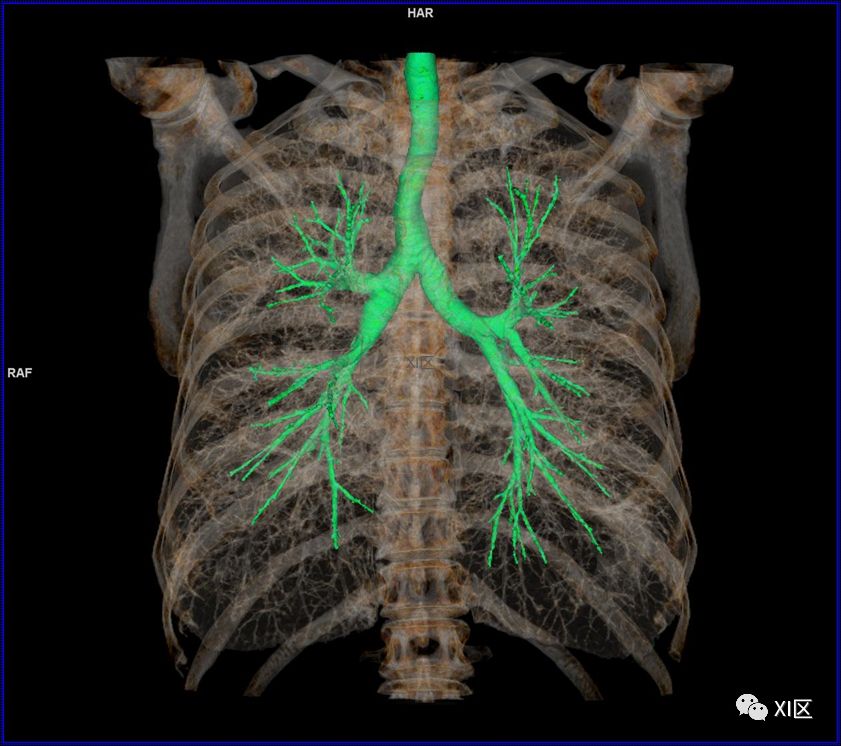

前后位,双侧位,后前位显示气道肺与胸部骨骼的关系

气管树

气管树与胸部其他结构的关系